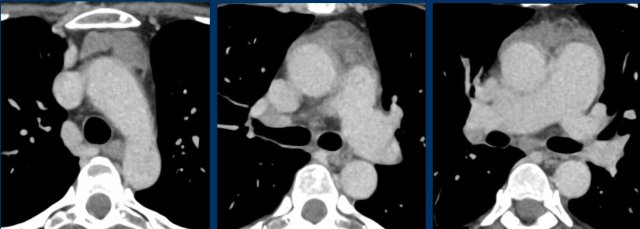

Case 2

These images are of a 43-year-old male with chest pain.

Images

There is a mass in the prevascular mediastinum.

The border is irregular and the lesion is positive on a PET-CT.

Discussion

The most likely diagnosis was a thymoma, probably invasive or even a carcinoma.

Continue with a preoperative scan two months later...

Two months later a preoperative scan was performed.

It is clear that the lesion is smaller.

However the surgeon decided to resect the lesion anyway and it turned out to be a thymus carcinoma.

We have no clear explanation for what happened here.

There is some reaction in the soft tissues surrounding the tumor on the first scan (arrow).

Maybe there was some inflammation within the tumor and surrounding tissues, which made the tumor look bigger.